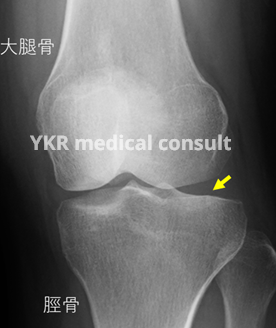

本件の画像評価の一部を掲載します。

本件では、受傷日と受傷翌日に撮影された各レントゲン写真や受傷後のフォロー目的で撮像されたMRI、事故後約11か月経過した時点で撮影されたレントゲン写真を精査し、脛骨の外側関節面に不整が残存していることを指摘した。これにより、「局部に頑固な神経症状を残すもの」として12級13号に相当すると意見した。